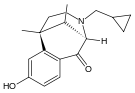

Benzomorphans

- 5,9 alpha-diethyl-2-hydroxybenzomorphan (5,9-DEHB)

- 8-Carboxamidocyclazocine (8-CAC)

- Alazocine

- Anazocine

- Bremazocine

- Butinazocine

- Carbazocine

- Cogazocine

- Cyclazocine

- Dezocine

- Eptazocine

- Etazocine

- Ethylketazocine

- Fedotozine

- Fluorophen

- Gemazocine

- Ibazocine

- Ketazocine

- Metazocine

- Moxazocine

- Pentazocine

- Phenazocine

- Quadazocine

- SKF-10047

Structures

| Benzomorphans | ||||

|---|---|---|---|---|

5,9 alpha-diethyl-2-hydroxybenzomorphan 5,9 alpha-diethyl-2-hydroxybenzomorphan (5,9-DEHB) |

8-Carboxamidocyclazocine 8-Carboxamidocyclazocine |

Alazocine Alazocine |

Anazocine Anazocine |

Bremazocine Bremazocine |

Butinazocine Butinazocine |

Carbazocine Carbazocine |

Cogazocine Cogazocine |

Cyclazocine Cyclazocine |

Dezocine Dezocine |

Eptazocine Eptazocine |

Etazocine Etazocine |

Ethylketocyclazocine Ethylketocyclazocine |

Fedotozine Fedotozine |

Fluorophen Fluorophen |

Gemazocine Gemazocine |

Ibazocine Ibazocine |

Ketazocine Ketazocine |

Metazocine Metazocine |

Moxazocine Moxazocine |

Pentazocine Pentazocine |

Phenazocine Phenazocine |

Quadazocine Quadazocine

|

Thiazocine Thiazocine |

Tonazocine Tonazocine |

Volazocine Volazocine |

Zenazocine Zenazocine |